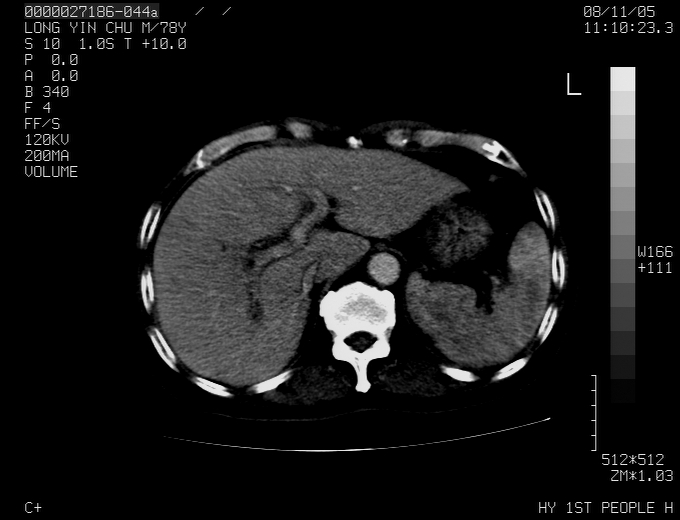

标题: CT16532:M78Y,肝脏病变,请会诊 [打印本页]

标题: CT16532:M78Y,肝脏病变,请会诊

腹胀,腹痛就诊,男性,78岁,外院b超未见异常。

肝ca,脾肾转移

支持脾肾转移瘤,双侧胸腔积液。

考虑弥漫性肝癌并脾及双肾转移.双侧胸水.

图片质量欠佳:多考虑:左侧肾癌。脾脏转移!胸膜转移!

肝脾肾转移瘤可能性大,左肾不除外梗塞,双侧胸水

考虑弥漫性肝癌并脾及双肾转移,双侧胸水。

考虑肝癌并双肾及脾脏转移;双侧胸腔积液。